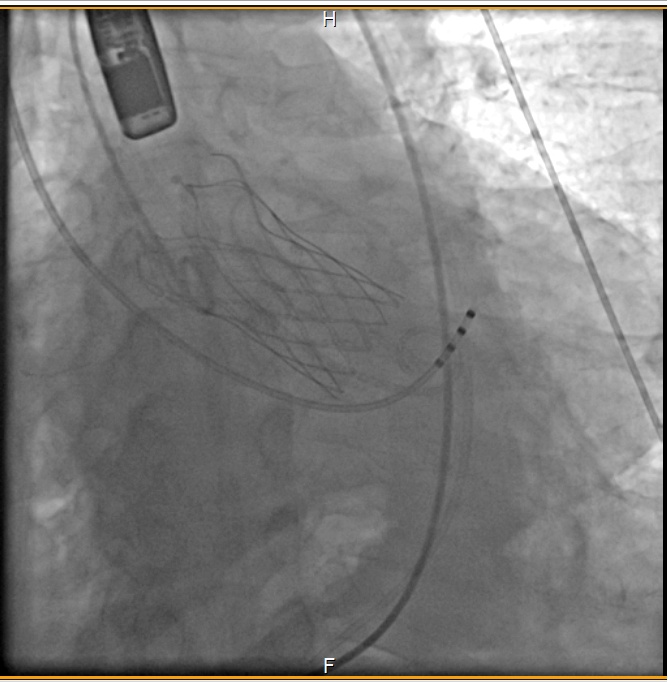

手术按计划进行,历时两个多小时,成功实施经导管主动脉瓣膜置换术,95岁患者董大爷获得新生。

在手术当天,杨先生被送往手术室进行TAVR手术。这种手术需要通过切口或血管插管将人工瓣膜送达到主动脉瓣位置。通过导管的引导下,人工瓣膜被展开并取代受损的瓣膜,恢复了心脏正常的血液流动。手术非常成功,杨先生的主动脉瓣问题得到解决。